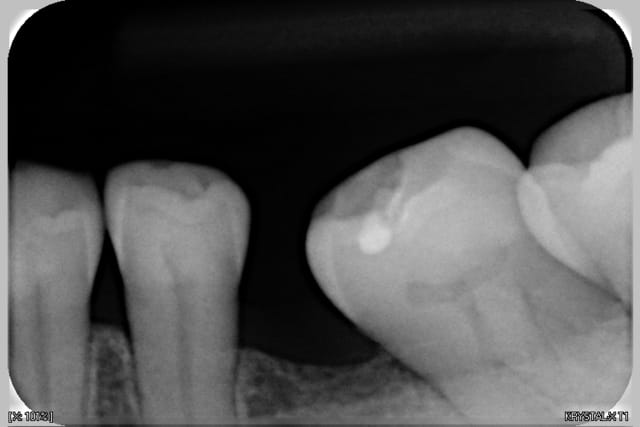

Voir images

On peut y voir une remodelage osseux, de tartre, l'usure de la canine

> On peut y voir une remodelage osseux, de tartre, l'usure de la canine

certes, mais le remodelage osseux est ancien, le tartre j'espère bien qu'il en reste plus depuis le temps (histoire que je serve à quelque chose)

faut il s'alarmer de tout épisode ancien de parodontite a part en sachant qu'il y a un risque de recidive et en faisant de la prévention ?